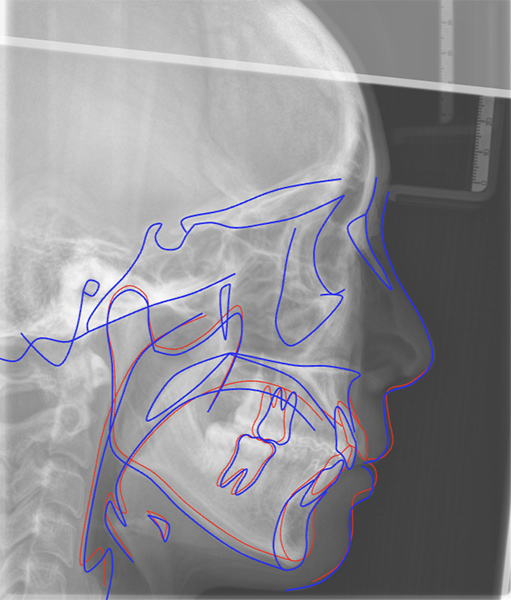

Pre- and post-treatment cephalograms are AI automatically superimposed.

Visually confirm skeletal and dental changes and accurately monitor treatment progress.

Easy-to-see treatment changes help patients better understand and accept their treatment plan.